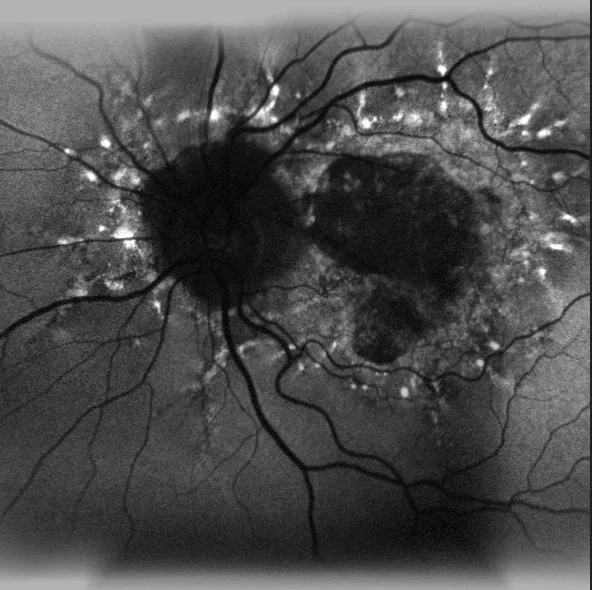

Analyse compréhensive

Trois scans automatiquement centrés sur la tête du nerf optique, utilisant le BMO, sont requis pour fournir des résultats hautement reproductibles de l’épaisseur de la couche des fibres nerveuses rétiniennes. Ces valeurs d’épaisseur sont comparées à une base de données normatives ajustée en fonction de la taille du BMO et l’âge du patient. La classification des secteurs de Garway-Health permet une meilleure corrélation entre l’épaisseur de l’anneau neurorétinien et les mesures fonctionnelles.

Le logiciel de segmentation multi-couches permet une évaluation de la couche des cellules ganglionnaires seules(GCL). Les résultats permettent une évaluation approfondie de la region maculaire par une carte d’épaisseur des cellules ganglionnaires.